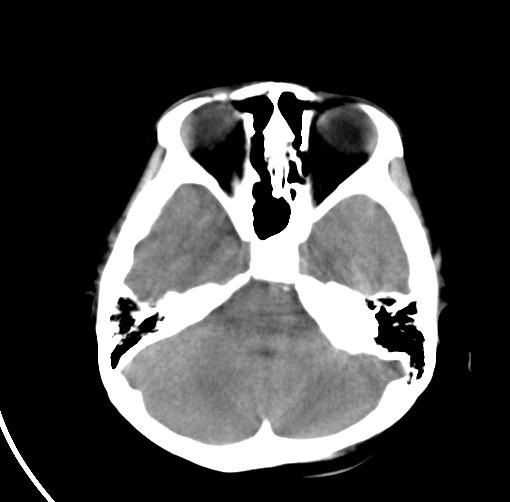

以下是引用sunjh2266在2007-7-31 23:35:00的发言:[br]脉络膜裂,是胚胎发育过程中脉络襞突入侧脑室下角构成脉络丛时形成,位于丘脑下部与海马之间,走行与海马平行。脉络裂内侧通于环池,外侧为侧脑室下角,前面是海马钩及杏仁体,后部与海马沟交通。脉络裂内有参与组成侧脑室脉络丛的脉络膜前动脉及脉络膜后外动脉及其分支走行。[br] mri轴位像,在大脑脚的前外侧多能显示脉络裂的前部,呈左右走行的含脑脊液间隙,前后内外分别与杏仁体、海马、海马钩及侧脑室下角相邻(图1);冠状位像,在扫及脑干的多个层面上,脉络裂均可被清晰显示,因而是显示脉络裂的最佳扫描方式。偏前的部分层面还可见到呈切迹状的海马沟走行于海马旁回内上方;矢状位像,海马旁回上方可见一分叉状裂隙,类似一斜卧的“入”字,接近水平走行的一撇为脉络裂,而由后上向前下走行的一捺为从扣带沟延续而来的海马沟。[br] [br]